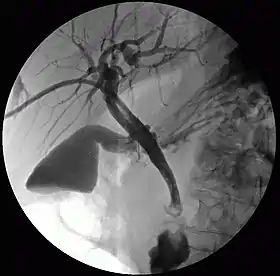

Cholangiography is the imaging of the bile duct (also known as the biliary tree) by x-rays and an injection of contrast medium.[1]

- Percutaneous transhepatic cholangiography (PTC): Examination of liver and bile ducts by x-rays. This is accomplished by the insertion of a thin needle into the liver carrying a contrast medium to help to see blockage in liver and bile ducts.